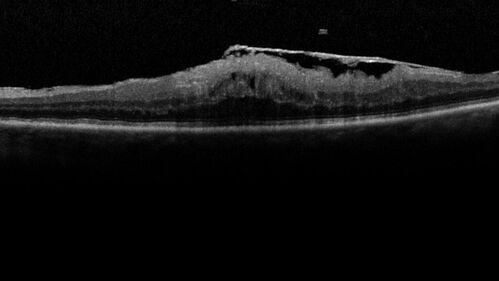

Elevated Episcleral Venous Pressure and Retinal Hemorrhages in both eyes

78 year old female with chronic red eye.   The eyes are red all the time now.  She is on Xeralto because of a history of blood clots in her lungs (2005 about).  She has not had problems since.  She has had floaters for many years.  Ever since her eyes got funny she sees more floaters in both eyes.  She had a brain scan over 6 months ago which was OK.  She also had double vision when this first started which went away.  She could not drive for a few months.

Neuroimaging did not show a CC fistula